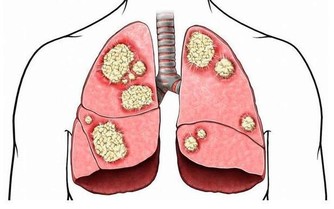

酒精容易引起酒精性肝炎、肝纖維化、肝硬化等情形,

而肝癌也是我國常見的惡性腫瘤之一,常見於中年男性。

因其惡性度高、病情進展快,病人早期一般沒有什麼不適,

一旦出現症狀就診,往往已屬中晚期。

而歐美等國家已有大量研究顯示,酒精與肝癌有著密切的關係,

而且,飲混合酒的人,患肝癌的機率比飲溫和酒或不飲酒的人高出5倍。

這是因為各種酒的酒精含量不同,

一會兒喝啤酒,一會兒喝烈酒、葡萄酒,身體對這樣的不斷變化難以適應。

更重要的是,各種酒的組成成分不盡相同,

比如,啤酒中含有二氧化碳和大量水分,與白酒混喝,會加速酒精在全身的滲透作用,

對肝臟、腸胃和腎臟等器官的刺激和危害就會更加強烈。